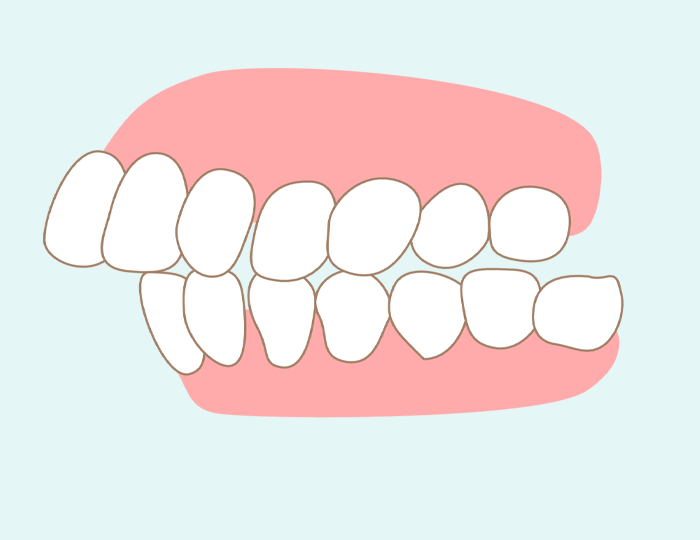

出っ歯

出っ歯は上顎前突(じょうがくぜんとつ)とも呼ばれており、文字通り上の歯が下の歯よりも前方へ出っ張った状態の歯並びをいいます。出っ歯の原因は、指しゃぶりを長期間し続ける、舌で上の前歯を押す癖があるなど、前歯を押し出す力が加わり続けることです。

出っ歯は外から見て非常に目立つため、子どものコンプレックスにつながりやすく、内向的な性格に育ってしまうケースがみられます。また、上唇が常に持ち上げられて口内が乾くことで、虫歯の発症リスクが高くなるという問題もあります。